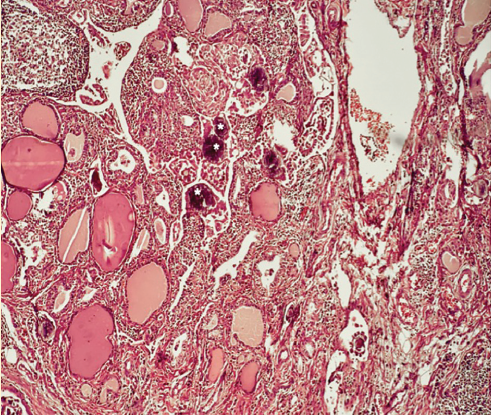

El reporte final de patología reveló formación difusa de folículos y papilas con cambios nucleares y abundantes cuerpos de psammoma en ambos lóbulos sin una cápsula identificable (figura 5), además de un nódulo de 5 mm en el lóbulo izquierdo con las mismas características, pero con formación de cápsula (figura 6).

Figura 5 Parénquima tiroideo con formación de folículos y papilas con cambios nucleares de CPT y abundantes cuerpos de psammoma (*).

Las microcalcificaciones se definen como ecos brillantes puntiformes finos sin sombra acústica8, los cuales tienen una correlación importante con el CPT9,10, Shi et al11 reportan una incidencia de cáncer de 96.5% cuando se identifican microcalcificaciones en los nódulos tiroideos. Estos ecos puntiformes se correlacionan en patología con los cuerpos de psammoma, los cuales se caracterizan por un proceso de calcificación distrófica con depósitos locales en tejido no viable con un calcio sérico normal. Los cuerpos de psammoma se identifican bajo el microscopio como estructuras calcificadas lamelares concéntricas que se presentan más frecuentemente en CPT, meningiomas y cistoadenocarcinoma papilar seroso de ovario12. Otra causa de ecos puntiformes en US son las calcificaciones distróficas características de la tiroiditis crónica. Whittle, et al.8 reportaron que 63% de los pacientes con microcalcificaciones difusas tuvieron CPT; cabe mencionar que 95% de sus pacientes presentaron un parénquima tiroideo heterogéneo sugestivo de tiroiditis crónica. Por lo tanto, un parénquima normal con ecos puntiformes difusos, como en el caso actual, debe obligar al clínico a realizar una BAAF con la sospecha de que estas representan la presencia de cuerpos de psammoma del CPT. Nuestro paciente presentó características típicas de CPT tanto por ultrasonido (microcalcificaciones) como por patología, lo particular del caso es la distribución difusa de las microcalcificaciones con ausencia de cápsula, hallazgos que no son descritos en la clasificación de la OMS6 y representa una variante del CPT convencional con algunos reportes de casos en la literatura8,10,13, en estos reportes se habla de un pronóstico similar a pacientes con CPT encapsulado dependiendo del estadio de presentación del mismo.